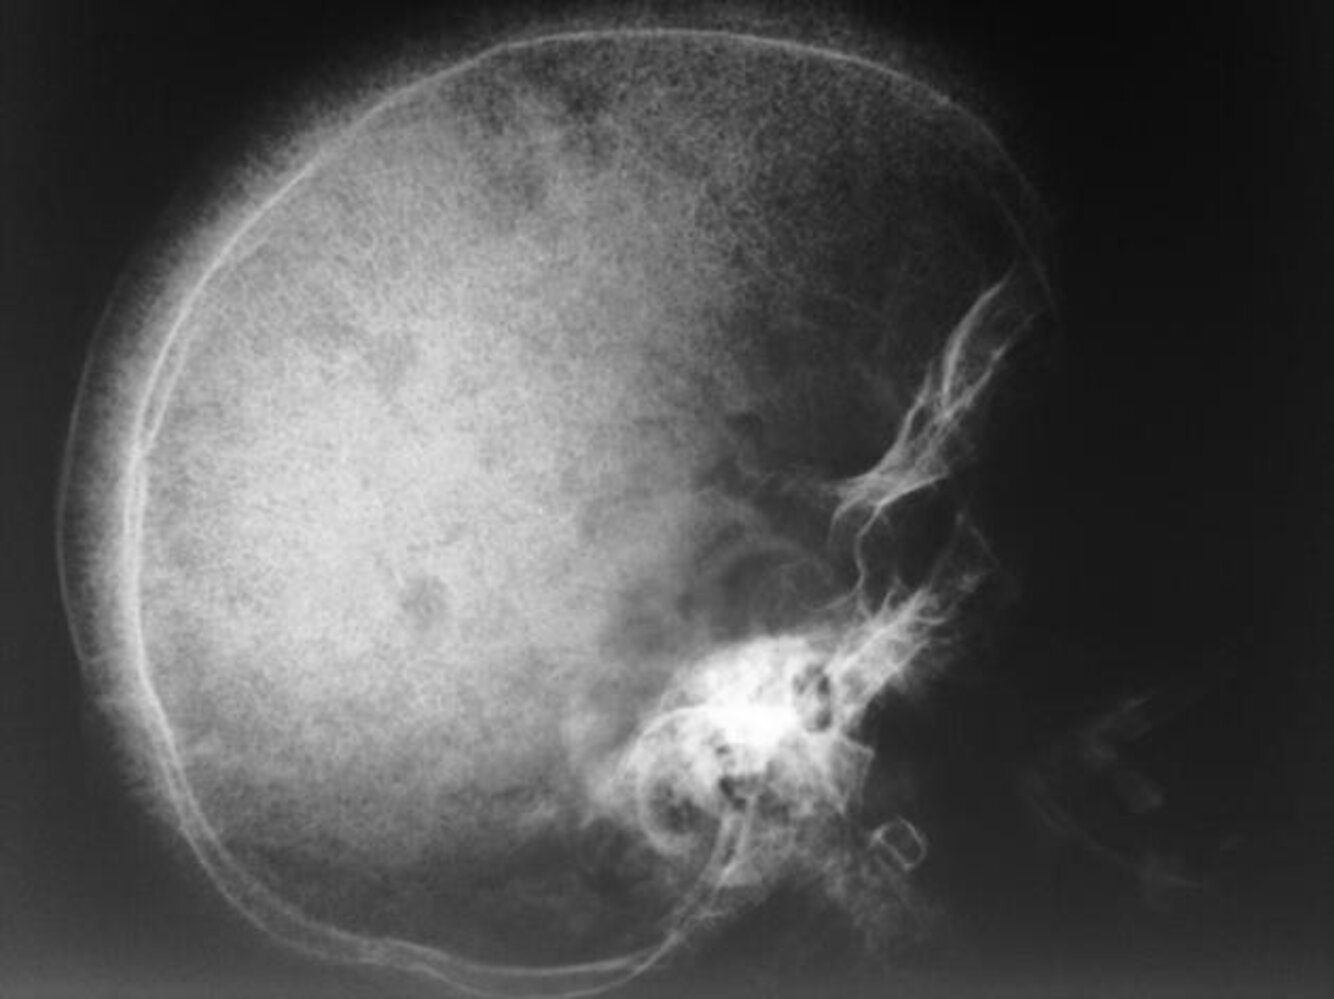

Skull x-ray [14]

• May show hair-on-end (“crew cut”) sign

• Caused by periosteal reaction to erythropoietic bone marrow hyperplasia

Hair-on-end appearance on skull x-ray may also be present in patients with thalassemia.